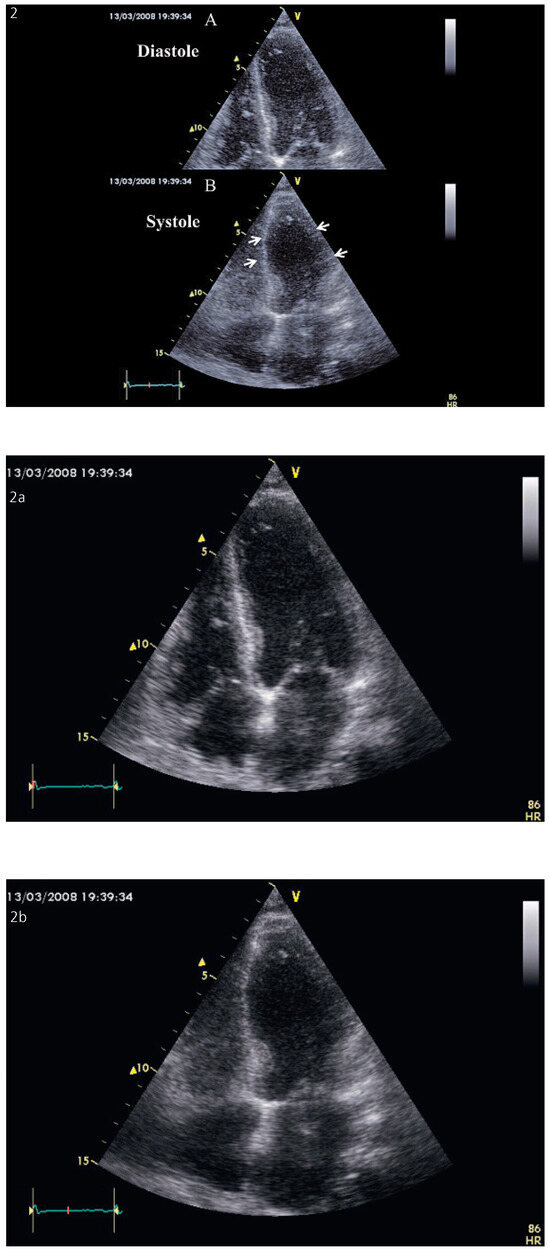

Background: Cardiac resynchronisation therapy (CRT) has become a mainstay in the treatment of patients with severe heart failure mainly due to large clinical trials demonstrating a reduction in morbidity and mortality. The aim of the present study wa...